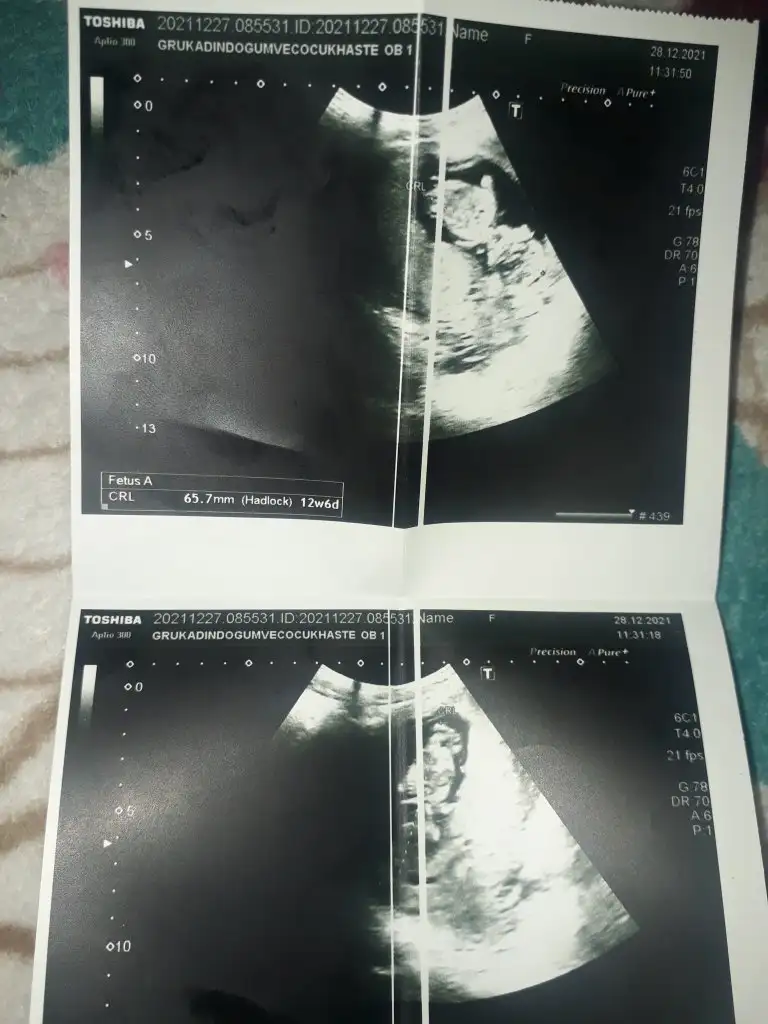

KızMerhaba sizce erkek mi kız mı 12 haftalığız :)

Çok teşekkürlerTahminim Erkek. Sağlıkla kucağına almak nasip olsun.

Bence erkek

Bugün doktora kıza benzetiyorum dedi kısmetTahminim Erkek. Sağlıkla kucağına almak nasip olsun.